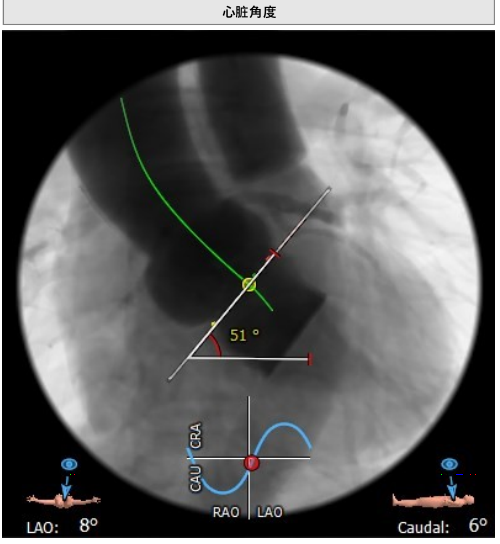

患者为功能型二叶瓣,重度钙化,左右融合,瓣环平面可见钙化延伸至左室流出道,冠脉高度高,法式窦结构大,心脏角度约51°,心肌增厚。

瓣环平均直径:25.6 mm,左室流出道平均直径:25.4 mm,升主动脉未见明显扩张,心脏角度:51°